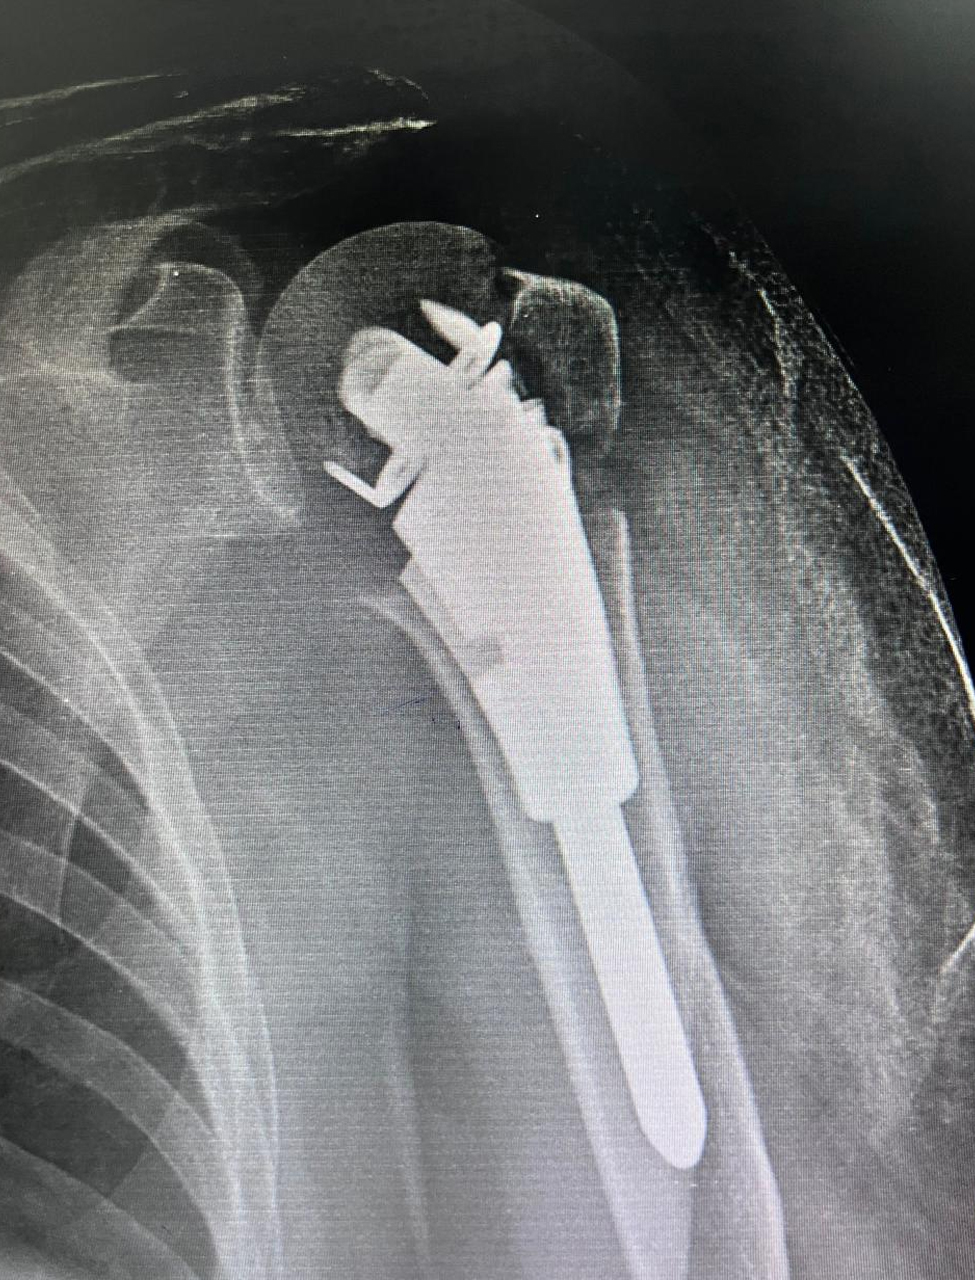

State new method of fixation of upper end humerus fracture using just unik